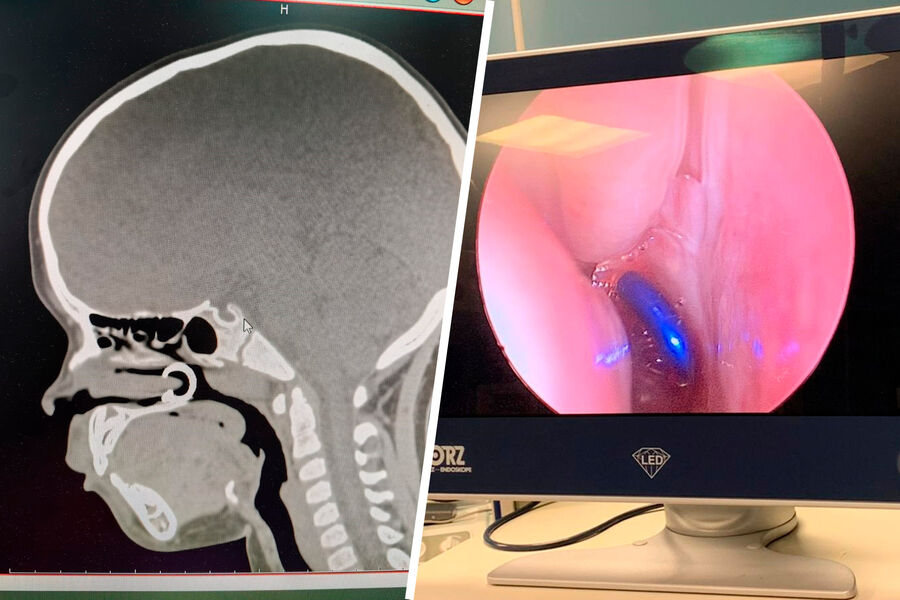

Rusiyanın Çuvaşiyanın Respublika Uşaq Xəstəxanasında həkimlər burnuna pirsinq sırğa taxmaq qərarına gələn və onu nəfəslə çəkən balaca qızı xilas ediblər.

Qızı Çuvaşiyanın Uşaq Klinik Xəstəxanasına gətirən balaca xəstənin valideynlərinin sözlərinə görə, qızı böyük bacısının ardınca getmək qərarına gəlib və burnuna pirsinq sırğası taxıb.

Yad cisim nazofarenksə düşüb, müayinə zamanı həkimlər sırğa aşkarlayıb endoskopik yolla çıxarıblar, heç bir cərrahi müdaxilə tələb olunmayıb.

Həkimlər xatırladıblar ki, uşaq yad cismi udubsa və ya tənəffüs edibsə, heç bir halda onu özünüz çıxarmağa çalışmayın, cisim tənəffüs yollarına daxil olarsa, təcili yardım çağırmalısınız, geri dönməz nəticələr mümkündür.